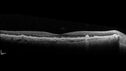

70-year-old Left eye worse than the right. Both eyes see distortion in the amsler grid for a few months

HTN, High Lipids, Osteoporosis

Meds: Lutein once daily, Calcium, Fish oil, Red Yeast Rice, CoQ10, Magnesium, MVI, Xanax

VA 20/16 OU

2+NS cataract